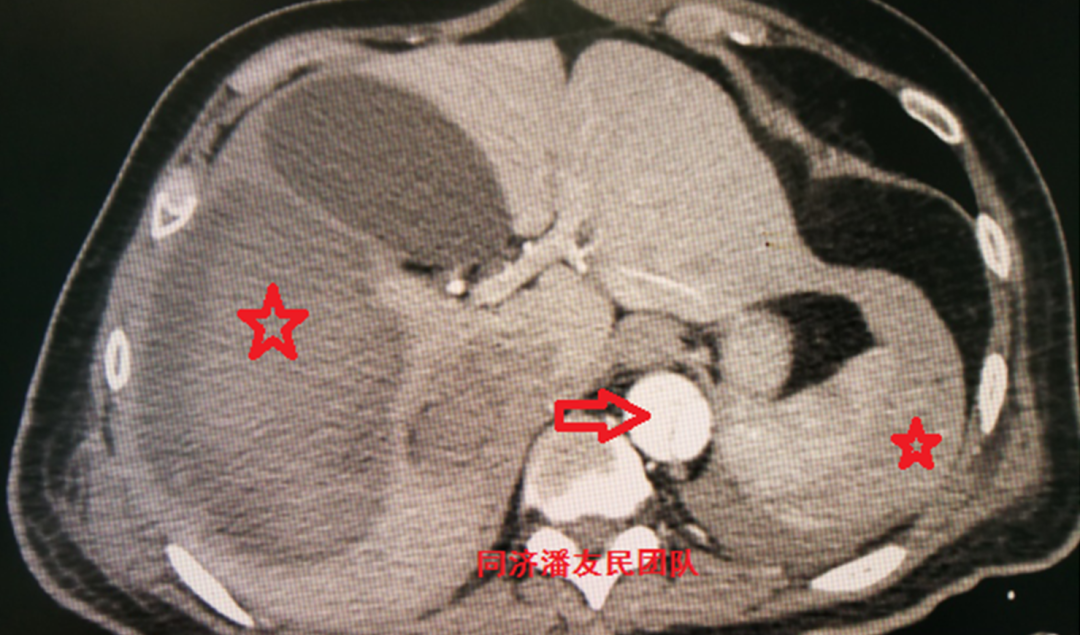

基层医院平扫CT提示胸降主动脉起始部内膜片影(图1),疑诊主动脉夹层(如何从平时CT发现主动脉夹层,请参考下文链接:没有CTA?这三招也能识别主动脉夹层!)。

图1:胸部平扫CT显示降主动脉管腔内可见内膜片(红箭头所示),考虑主动脉夹层。同时显示纵隔血肿(红星号)及左侧少量胸腔积液(白箭头所示)。

入院后,胸腹主动脉CTA将主动脉及胸腹腔脏器一起进行全面评估。与图1平扫CT层面对应,图2显示降主动脉夹层。

图2:与上图1平扫CT层面相对应,红箭头显示降主动脉夹层,红星号显示纵隔血肿,白箭头显示胸腔积液。